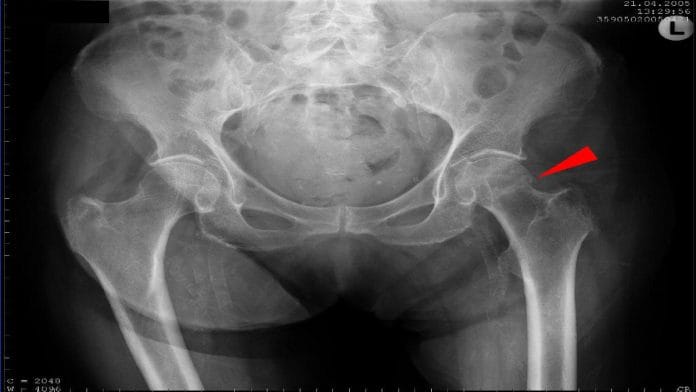

According to the team, incidences of thigh-bone and hip fractures have increased significantly due to the increasing geriatric population in the world. An estimated 2 lakh hip fractures occur every year in India alone, most of which require hospitalisation and trauma care.

Traditionally, treatment for hip fractures includes bone plates and rods to bridge the fracture site and promote bone healing. Fracture treatment methods are intuitively chosen by surgeons based on their experience, and there is no way of predicting the efficacy and success of the treatment method chosen.